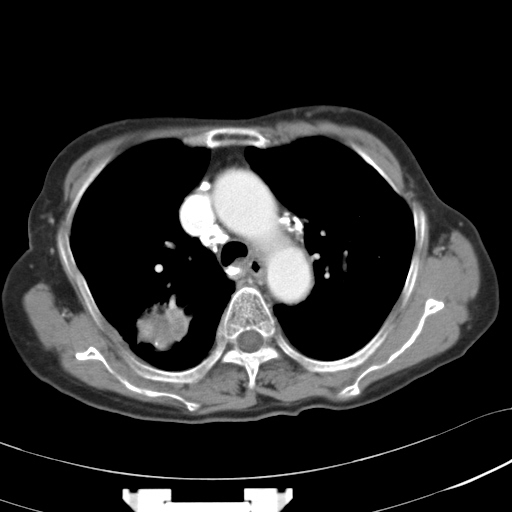

以下是引用hhcckk在2007-3-2 14:51:00的发言:[br]考虑结核球可能性大,依据[br]1病灶在下叶背段,结核的好发部位[br]2病灶内有大量的钙化,纵隔内有大量的淋巴结钙化[br]3重要的是半年前与现在相比无变化,假如是肿瘤的话不会这么‘善良’[br]4病灶周围卫星灶不明显,病灶有毛刺,胸膜凹陷,肿瘤不能完全排除,有条件的话最好做个活检

以下是引用liuyue在2007-3-2 17:15:00的发言:[br]1位置:右上叶后段[br]2性质:大分叶、粗长毛刺、条状斑片状钙化、纵隔多发淋巴结钙化,无强化,故考虑:肺结核灶(陈旧)